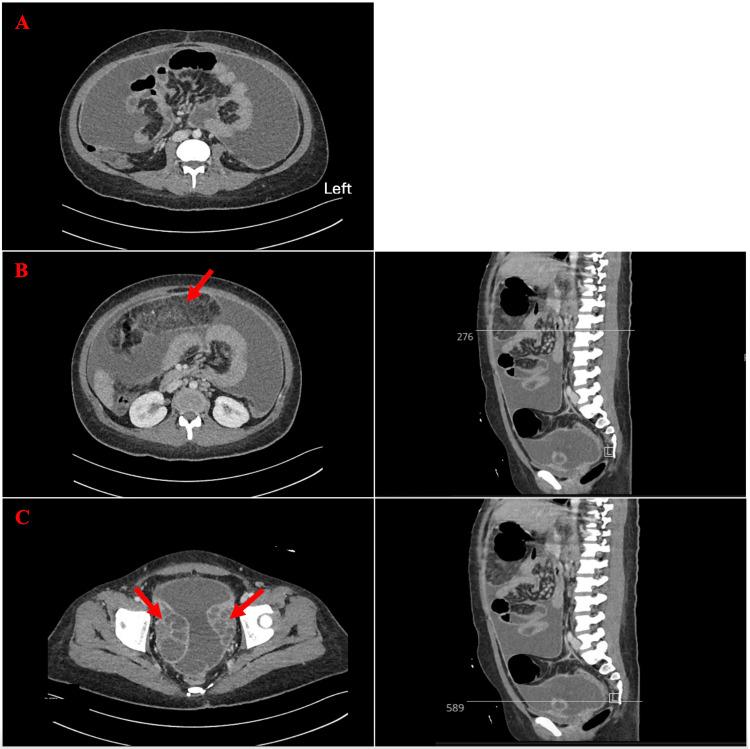

Tuberculosis (TB) is caused by . It is a multisystem infection, but the most common manifestation is pulmonary. TB is the leading cause of death among infectious diseases. Abdominal TB is a form of extrapulmonary TB (EPTB) that often presents nonspecifically and can result from genitourinary or hematogenous spread. We present the case of a 20-year-old Bangladeshi woman who presented with a two-month history of fever and night sweats accompanied by vomiting, tachycardia, and tachypnea. Laboratory investigations revealed elevated inflammatory markers, lactate dehydrogenase, and cancer antigen 125. QuantiFERON-TB (QIAGEN N.V., Venlo, Netherlands) was positive. An abdominal ultrasound showed free fluid throughout the abdomen. A CT scan of the abdomen revealed thickening and enhancement of the peritoneum, omental caking, and bilateral bulky ovaries measuring up to 8.5 x 5.4 cm on the right side, raising suspicion of malignancy. However, an MRI showed that the pelvic masses were, in fact, bilateral hydrosalpinx. Peritoneal analysis indicated a serum ascites albumin gradient (SAAG) of less than 1.1, suggesting peritonitis with neutrophil predominance. Acid-fast bacillus (AFB) culture of the peritoneal fluid grew . Abdominal TB and ovarian cancers can overlap in clinical presentation, especially in young female patients. Imaging may be misleading, as seen in this case. Imaging modalities may assist in the diagnosis; further exploration, particularly diagnostic laparoscopy with biopsy, is required for suspected ovarian cancer and EPTB.

结核病(TB)由……引起。它是一种多系统感染,但最常见的表现是肺部感染。结核病是传染病中主要的死亡原因。腹部结核是肺外结核(EPTB)的一种形式,通常表现不具特异性,可由泌尿生殖系统或血行播散引起。我们报告一例20岁孟加拉国女性病例,该患者有两个月发热、盗汗病史,伴有呕吐、心动过速和呼吸急促。实验室检查显示炎症标志物、乳酸脱氢酶和癌抗原125升高。结核菌素定量检测(QIAGEN N.V.,荷兰芬洛)呈阳性。腹部超声显示全腹有游离液体。腹部CT扫描显示腹膜增厚、强化,网膜饼状增厚,双侧卵巢肿大,右侧最大径达8.5×5.4cm,怀疑为恶性肿瘤。然而,磁共振成像显示盆腔肿块实际上是双侧输卵管积水。腹膜分析显示血清腹水白蛋白梯度(SAAG)小于1.1,提示以中性粒细胞为主的腹膜炎。腹膜液抗酸杆菌(AFB)培养长出……。腹部结核和卵巢癌在临床表现上可能重叠,尤其是在年轻女性患者中。如本病例所示,影像学检查可能会产生误导。影像学检查方式可能有助于诊断;对于疑似卵巢癌和EPTB,需要进一步检查,特别是诊断性腹腔镜检查及活检。